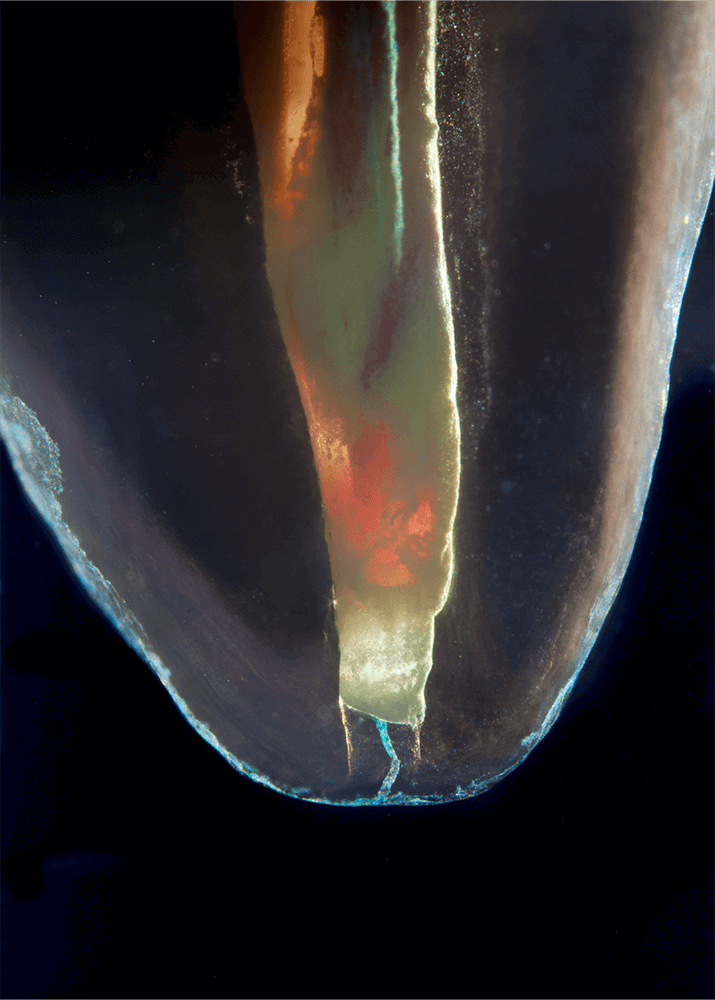

Transparente Zahnpräparate

Bilder transparenter Zahnpräparate

Das Verfahren, Zähne in durchsichtige Präparate zu überführen ist schon über 100 Jahre alt. Aber erst durch die Weiterentwicklung der alten Technik und die Kombination mit moderner Fotografie sowie der Entwicklung eines geeigneten Gefäßes zur Fotografie ist es meinem Vater Dr. Holm Reuver gelungen, einzigartige Bilder vom Inneren der Zähne aufzunehmen.

Die Bilder sind in verschiedenen Größen wählbar und auch als POPART-Variante erhältlich. Sie sind hervorragend geeignet für die Beratung von Patienten vor endodontischen Behandlungen, aber auch ein beliebter Eyecatcher im Wartezimmer. Außerdem haben die Bilder einen bedeutenden Stellenwert für die Erforschung der Pulpatopografie und für die Lehre im Bereich der Endodontie.

CLEARINGSERVICE bietet Ihnen die Möglichkeit, wurzelgefüllte Zähne mit der Technik des Transparentmachens untersuchen zu lassen. Das geht sehr einfach: Sie schicken uns den zu untersuchenden Zahn, dieser wird dann in ein transparentes Präparat überführt und mit hochwertiger Makrofotografie ausgewertet. Anschließend bekommen Sie die angefertigten Präparate zusammen mit der Fotodokumentation zugeschickt.